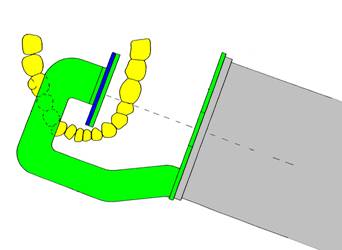

Técnica

paralela para la toma radiográfica periapical ó

del cono largo:

-

El diente

debe estar tan paralelo y cercano a la

película como sea posible, y

-

La fuente

de los Rayos X debe ser pequeña y estar tan

lejos del diente como sea posible.

|